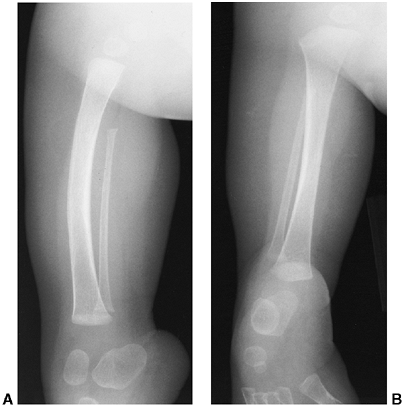

Figure 31.3 A, B:

The radiographs of a 3-month-old boy with type IA fibular deficiency of the Achterman and Kalamchi classification. Although the bones may seem normal to the casual observer, the proximal fibula is short. C, D: Anteroposterior and lateral radiographs of the same patient at the age of 7 years, 6 months. The shortening of the fibula is more apparent and the ball-and-socket ankle joint is easily seen. E: The foot at the same age, with the lateral two rays missing. F: At 13 years of age, the leg was lengthened by 7 cm. |

shortened in relation to the tibia. This may occur either proximally or

distally or both (Fig. 31.3). Often a portion of the fibula is absent in part (Fig. 31.4) or in its entirety (Fig. 31.5).

In those cases in which the fibula is of normal or near-normal length,

the diagnosis can be difficult during the first year of life.